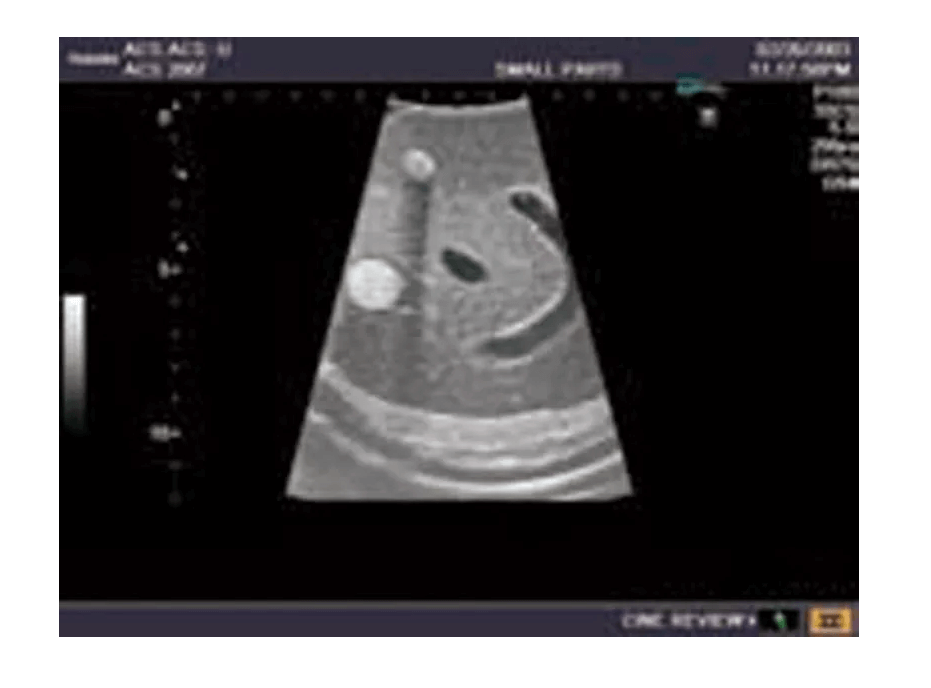

Das Ultraschall-Modell für Sonografie ist speziell für die Ausbildung von Anfängern und die Demonstration durch Fachleute konzipiert. Es bietet eine detaillierte und realistische Darstellung der Anatomie des Abdomens, einschließlich der Leber, Gallenwege, des Pankreas und der Nieren. Das Modell erfüllt die höchsten Anforderungen an eine exzellente Ausbildung und ermöglicht die Durchführung von offenen intraoperativen Sonografien sowie laparoskopischen Untersuchungen, um etwaige Läsionen und Steinbildungen zu prüfen. Es umfasst eine Vielzahl von Läsionen wie Gallensteine, Zysten und Tumore, die in den verschiedenen Organen simuliert sind, um realistische Übungsmöglichkeiten zu bieten.

Modell enthält eine detailgetreue Darstellung von Gefäßstrukturen wie Aorta, Vena cava, Vena portae und Nierengefäßen

Der Behälter des Modells ist mit Wasser befüllbar, was eine realistische Simulation von Kontakt- und Abstandstechniken ermöglicht

Das Modell stellt fast lebensgroße Organe und Strukturen dar, sodass realistische und präzise Übungsszenarien durchgeführt werden können